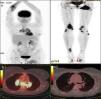

| Supplemental tests | ACE>100 (NV 8–52mg/dl).PET: cutaneous, mediastinal lymph node, pulmonary, bone and muscle involvement (Fig. 1) | ACE>100mg/dlPET: mediastinal lymph node, pulmonary and bone involvement | ACE>100mg/dlCT: pulmonary and lymph node involvement |

Nuclear medicine study of case no. 1. (A) Scintigraphic study showing an active inflammatory process affecting upper and lower limbs, mediastinal lymph nodes, lung parenchyma, bone and left gluteal muscle. (B.1) Positron emission tomography (PET) study showing mediastinal lymph node involvement prior to treatment. (B.2) PET study following treatment.

Positron emission tomography currently constitutes a useful tool in the diagnosis and follow-up of sarcoidosis, even in cases of occult or asymptomatic involvement. It is more sensitive and requires a 3-fold lower radiation dose than gallium scintigraphy.9